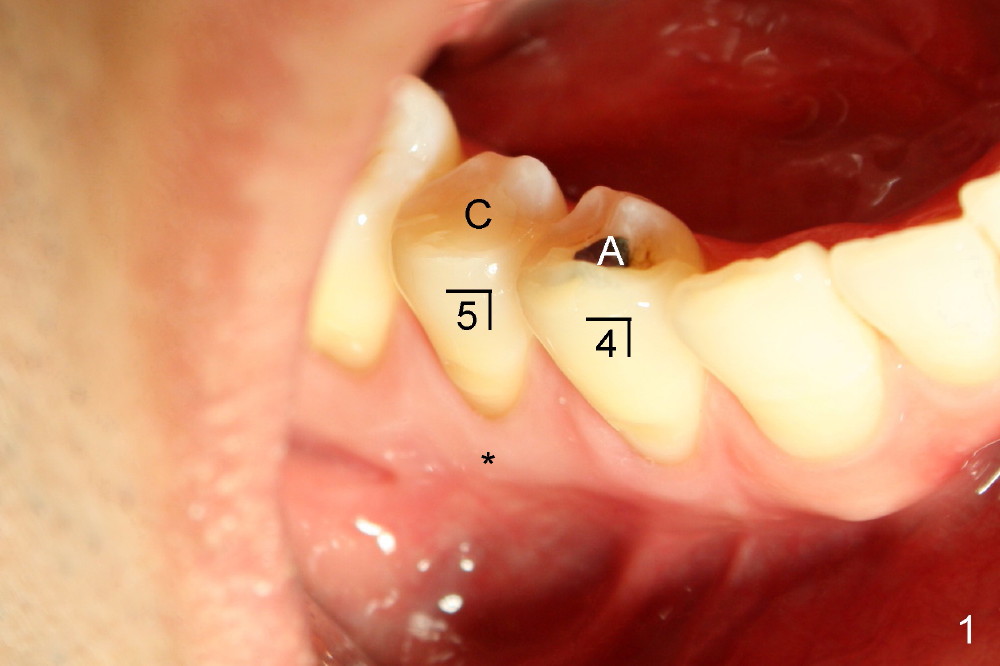

图一,二是治疗结束后两年拍摄的,其实右下第二双尖牙也作过根管治疗(图一),开口也由树脂修复(C),第一双尖牙在国内用银汞修复(A,没做根管治疗,所以牙齿没有变色)。图一,二最大不同的是右下第一双尖牙根部没有萎缩(图一*),而左下同样地方(植牙)明显凹陷(图二箭头),这可能说明尽管植牙,骨头还会萎缩。更准确地说萎缩是由于术前根尖病变所致,为了尽量减少这个趋势,拔牙后应该马上植牙,或者植骨。